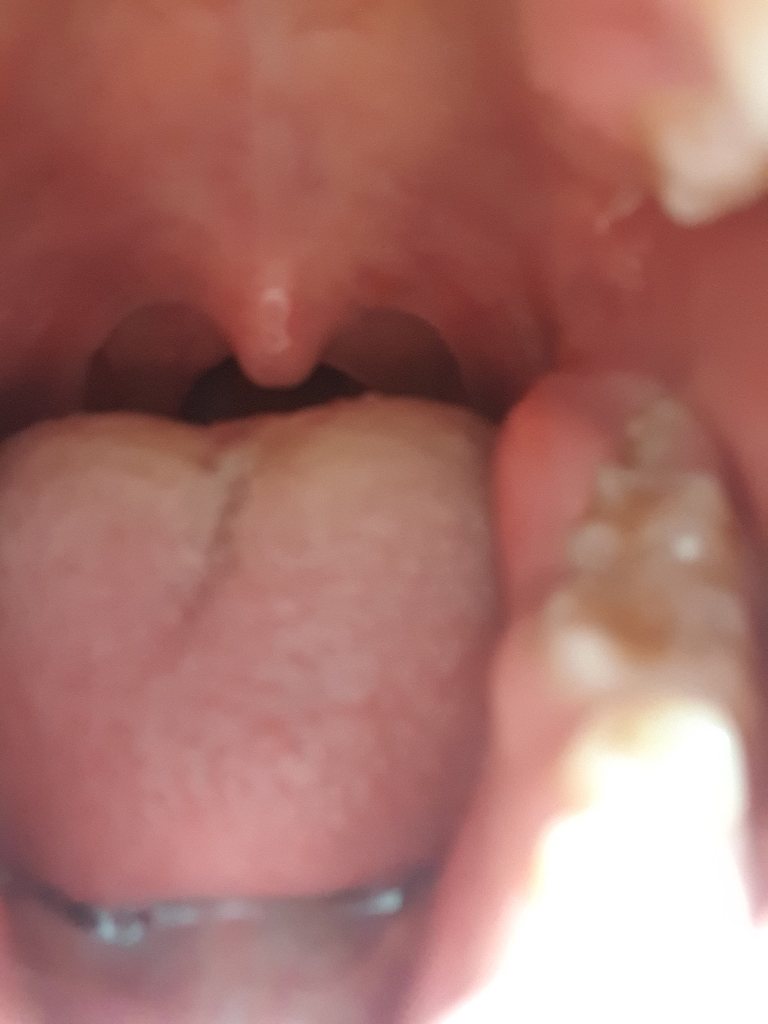

사랑니쪽 잇몸이 많이 부었고 무슨 고름같은게 나오는것 같습니다. 치과를 가야할까요?

사랑니쪽 잇몸이 붓는건 자주있는 일이라 항상 그냥 냅뒀는데 며칠전부터 부은 부위에서 무슨 맛이 상시 느껴집니다. 혀로 부은 부위를 누르면 더욱 많이 느껴지고요. 아마 고름인것 같은데 이거 치과 가야하나요? 그냥 냅둬서는 회복이 안되는건가요?

• 1번 째 사진

사랑니 주위 잇몸에 염증이 있는 것으로 보입니다. 치과에 가서 치료하고 항생제 복용해야 합니다. 잇몸 부은 것이 가라앉은 후에는 사랑이 뽑아야 합니다.

사랑니염증은 방치하면 사랑니뿐만 아니라 앞의 어금니까지 발치해야할 수 있습니다

사랑니가 부분적으로 맹출되서 잇몸안쪾으로 음식물들이 들어가서 제대로 제거가되지 않아 그쪽에 염증이 생긴거 같습니다. 치과에 가셔서 먼저 잇몸치료를 받으시고 계속 불편하시면 사랑니를 발치하시는게 좋을것같습니다.